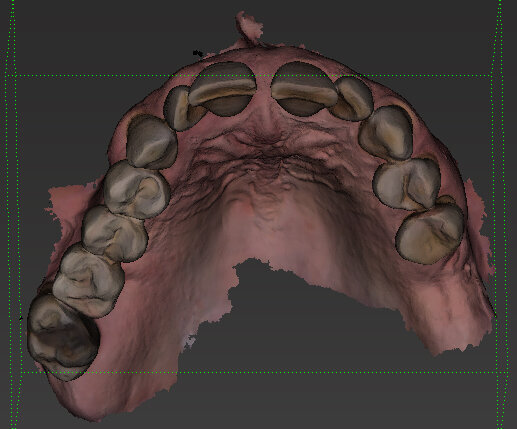

Il piano di trattamento prevede l’estrazione degli elementi dentali, l’inserimento di due impianti e la realizzazione di una protesi fissa di quattro elementi. Il problema da gestire è quello della fase provvisoria. Non è ipotizzabile una protesi mobile e quindi programmiamo di inserire subito dopo l’intervento un provvisorio immediato. Questo ci consente di condizionare da subito i tessuti periimplantari e anche le zone dei ponti. Si rileva un’impronta digitale (Figg. 5, 6), e la programmazione degli impianti viene effettuata con un software di chirurgia guidata (Fig. 7) e la posizione degli impianti nello spazio biologico e nello spazio protesico viene fatta sulla base di una ceratura diagnostica (Figg. 8, 9). Inseriamo gli impianti virtuali nell’osso disponibile (Figg. 10-13) e in relazione all’aspetto protesico correggiamo l’asse di inclinazione degli impianti con componenti secondarie angolate a 17° (Figg. 14, 15). Questo ci consentirà di realizzare una protesi avvitata con i fori situati nella zona palatale.

Fig. 6 - Visione occlusale.